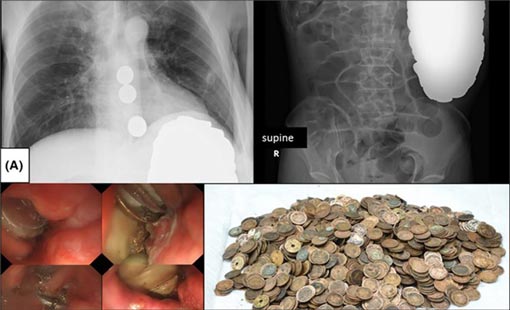

وقد أثبت فحص الأشعة في مستشفى بطوكيو وجود أجسام دائرية في المعدة، وتقرّر على إثر ذلك إخضاعه لعملية جراحية مستعجلة، فاكتشف الأطباء مذهولين وجود قطع نقدية معدنية داخل معدة المريض وبدؤوا على الفور استخراجها.

عثر الأطباء على 1894 قطعة معدنية بوزن يفوق ثمانية كلغ، منها 140 قطعة من فئة ين ياباني واحد، و99 من فئة الخمسة ينات، و1642 من فئة عشرة ينات، و8 من فئة خمسين يناً، وخمس قطع من فئة مئة ين، ويبلغ مجموع ما استخلص من بطن المريض نحو 157 دولاراً.